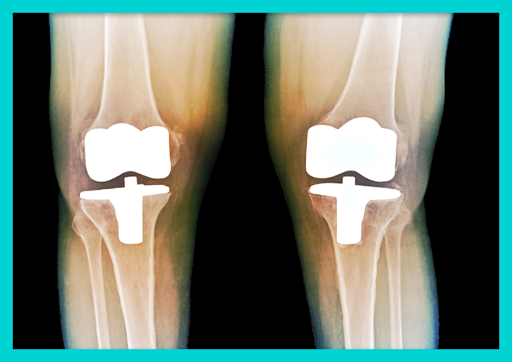

무릎 인공관절 수술 성공률과 장기 효과

📊 수술 성공률

전체 성공률

✅ 95-98%의 높은 성공률

⏰ 인공관절 수명

🔧 기간별 생존율